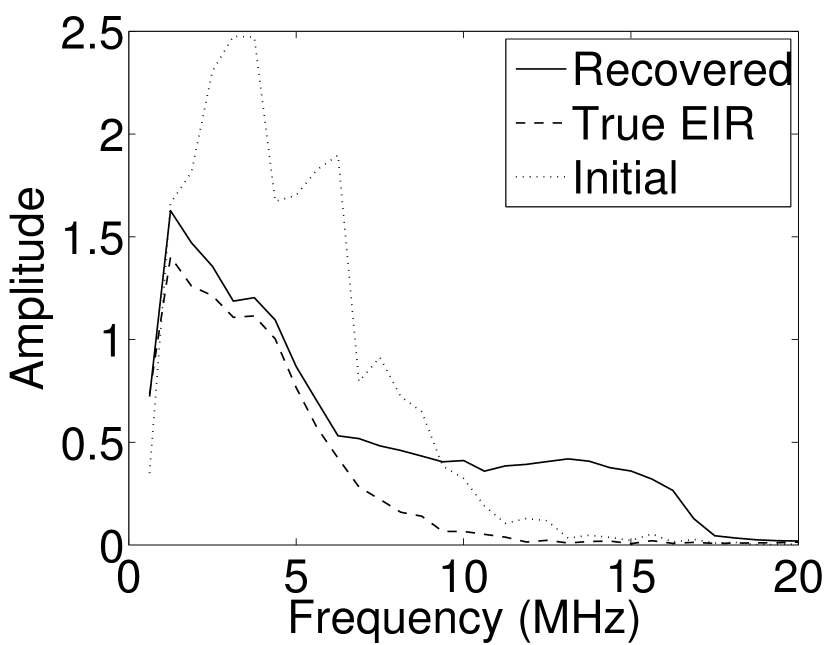

Figure 7(a) reveals that use of the inaccurate EIR in the conventional iterative method created strong artifacts and distortions. Figures 7(b) confirms that the artifacts and distortions were significantly mitigated when the VP method was employed. Image profiles for both cases are shown in Figures 7(c). The overall accuracy of the recovered EIR, shown in Figure 7(d) and 7(e), was improved, but it contained spurious oscillations.

Images reconstructed by use of the VP algorithm with different values of the regularization parameter values are shown in Figure 8. The recovered EIRs and their corresponding Fourier spectra are shown in Figures 9 and 10, respectively. The RMSE values are computed and displayed together with the corresponding images. As expected, the images reconstructed with smaller values of contain higher noise levels, while images using larger possess a reduced noise level. However, larger values of also caused artifacts in the reconstructed images. The same observation can be made for the effect of the regularization parameter on the recovered EIR. One also observes that the reconstructed images and EIRs depend continuously on the regularization parameters and , i.e. small changes in the regularization parameters cause minor changes in the reconstructed images and EIRs.